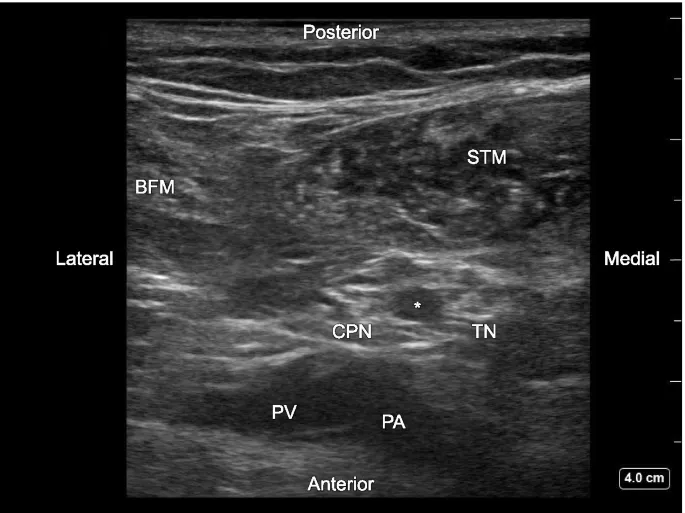

Popliteal Block (Sciatic in fossa): TN & CPN targeted.

- For: Foot, ankle, calf surgery. Spares quads & hamstring motor.

- Approaches: Posterior (prone/lat), Lateral (supine).

- Vol: ~20 mL total; or ~10 mL each TN/CPN.

- ⚠️ CPN injury risk (superficial/lateral) → foot drop.